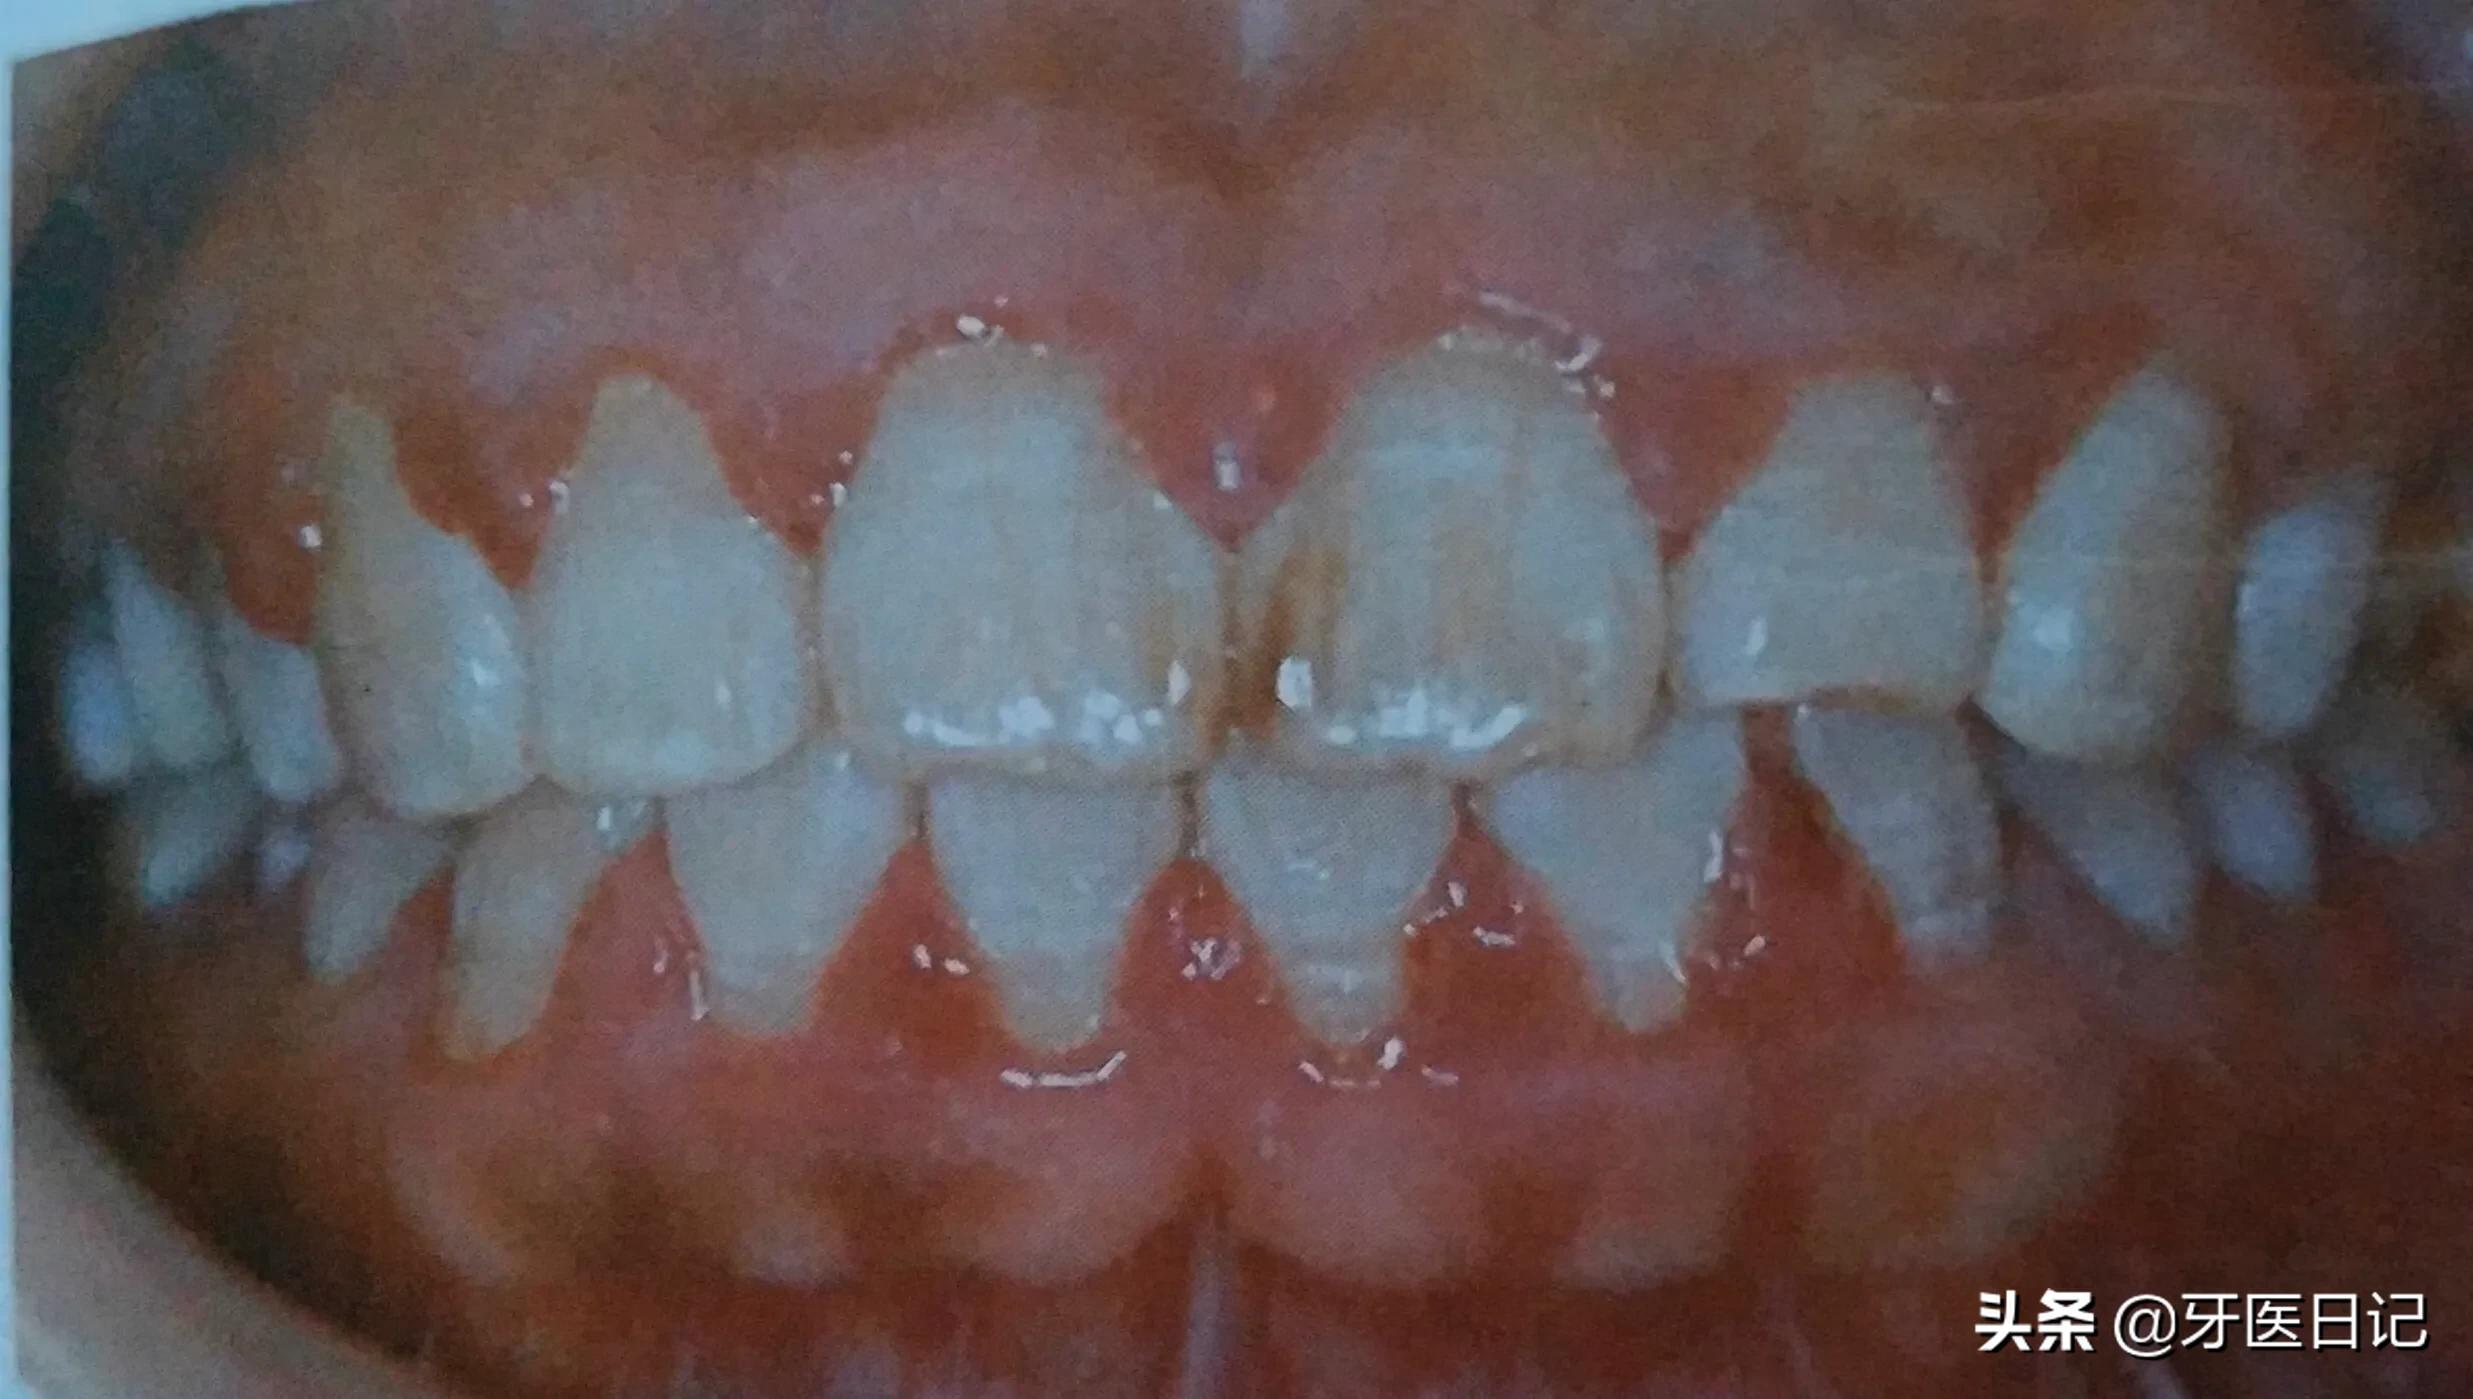

①牙龈的炎症:主要表现为牙龈出血,可以表现在刷牙时、咬东西时、严重者可在无任何刺激的情况下出血。

最常见的是口腔卫生不洁,有牙结石的存在,牙结石压迫刺激牙龈,导致牙龈红肿、出血,特别在青春期的同学,或者孕期的女性常会因激素水平的改变而出现青春期牙龈炎和妊娠期牙龈炎,其主要表现就是牙龈红肿和出血,而普通人的牙龈红肿出血多是牙结石刺激导致,当然一些系统疾病也会导致牙龈出血,如白血病。